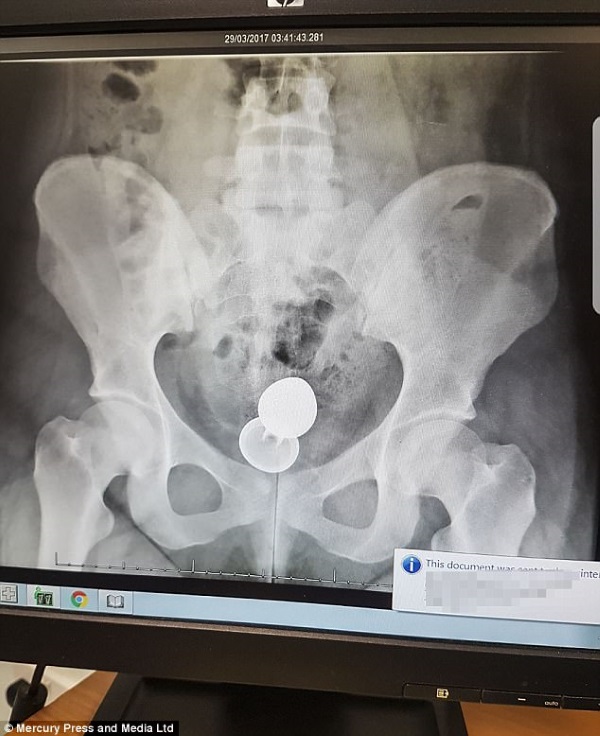

Los facultativos en un principio le dijeron que la operación podía ser más complicada de lo que realmente fue. Le hicieron una radiografía donde se veía el objeto, que pudo comprometer la salud de Emily.